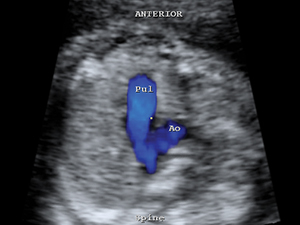

Heart